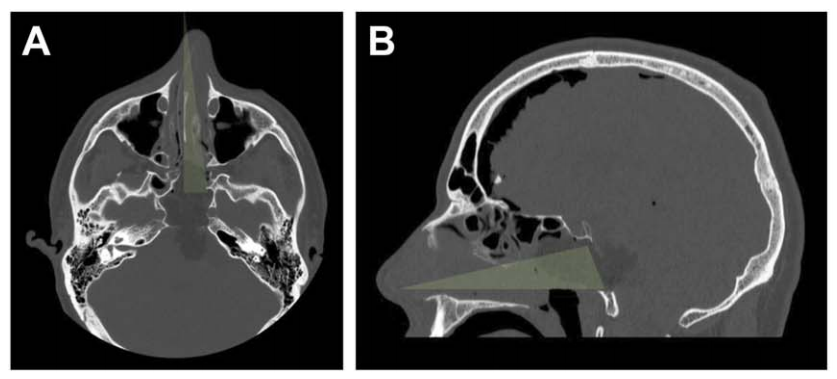

最终,在INC福教授的定制化手术策略之下,从术前栓塞、入路考量到实施手术,无需开颅,仅右侧单鼻孔入路,一双“筷子”便成功全切肿瘤。脑干复位良好,未见脑嵴液漏及新发神经功能障碍,术后一天下地,术后一周顺利出院。关闭术腔时,以腹部脂肪填塞硬膜内腔及蝶窦,并缝合鼻黏膜,表面覆盖硅胶片保持湿润;硅胶支架留置4周后取出。

A、B:术后CT轴位及矢状位,绿色显示单鼻孔入路,鼻腔完整性得以保持;鼻中隔、上颌窦、后组筛窦及左侧蝶窦间隔均完整。